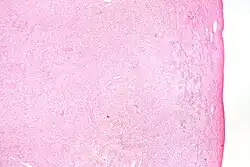

Caractéristiques pathologiques

Grossièrement, la tumeur est solide et jaune.

Grossièrement et au microscope, il se compose du cortex ovarien.

Au microscope, les cellules tumorales ont un cytoplasme abondant rempli de lipides.